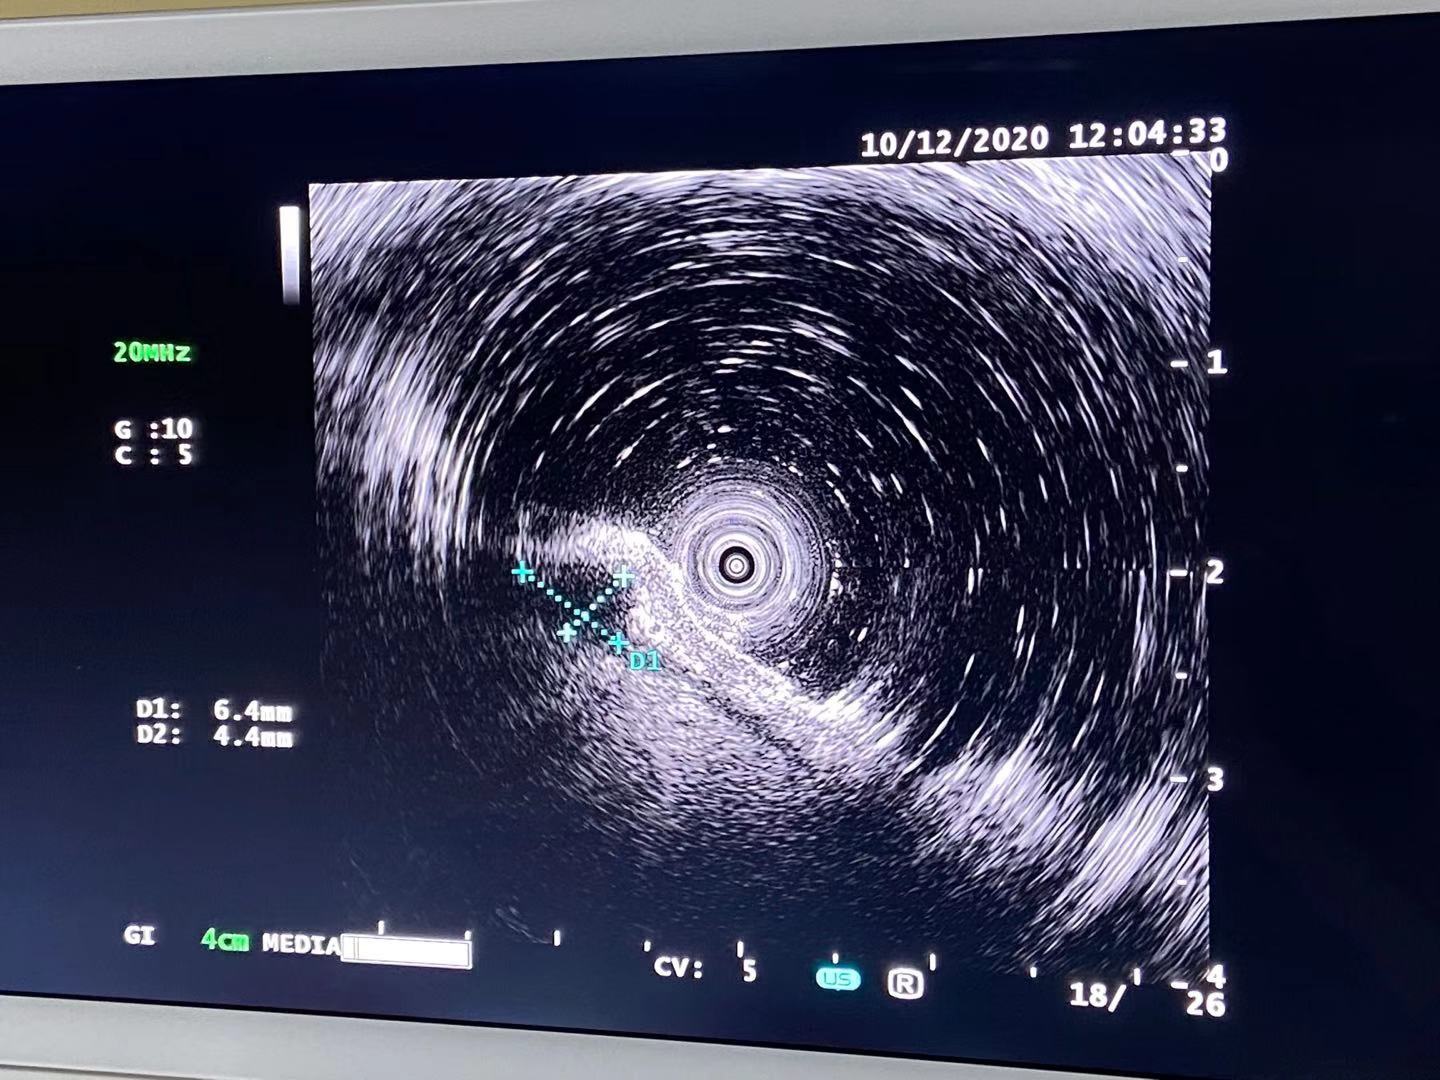

12月1日,广德市人民医院引进了最先进的超声内镜系统奥林巴斯EU-ME2,这是超声内镜首次亮相广德市。

12月10日,贾玉良院长带领消化内科成功完成我院首例胃、十二指肠病变超声内镜检查,标志着市人民医院消化内科又一诊疗技术的成功开展。

超声内镜是什么? 超声内镜(EUS)是内镜和超声相结合的消化道检查技术,将微型高频超声探头安置在内镜顶端,当内镜插入体腔后,在内镜直接观察消化道粘膜病变的同时,可利用内镜下的超声行实时扫描,可以获得胃肠道的层次结构的组织学特征及周围邻近脏器的超声图像,从而进一步提高内镜和超声的诊断水平,扩大了消化内镜视野,拓宽了消化内镜的诊疗范围。